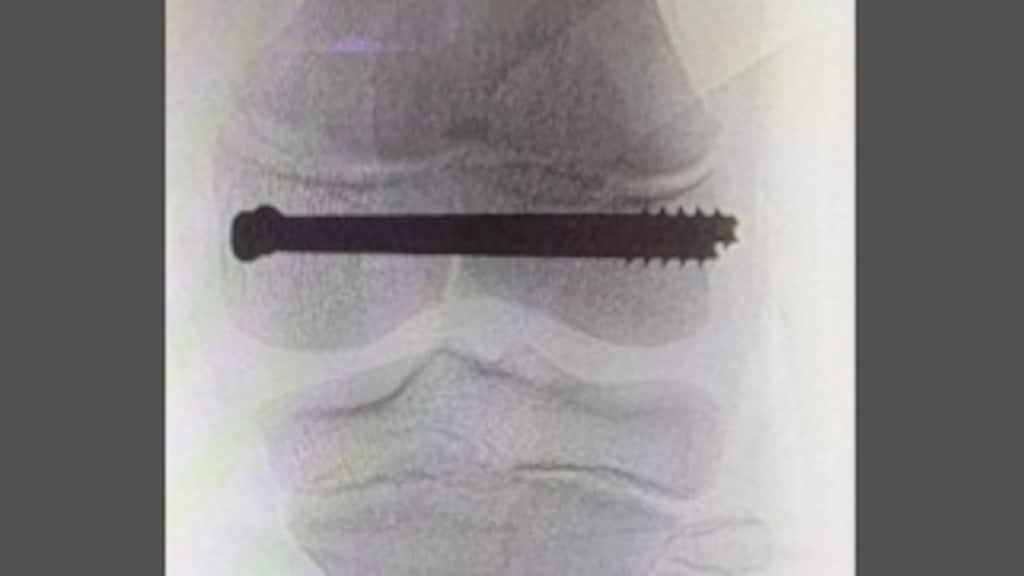

De huisarts stuurde hen naar het ziekenhuis, waar foto's en een scan werden gemaakt. Het been van Amir werd van zijn lies tot en met zijn tenen in het gips gezet om de pijn te verzachten. Uit de resultaten van een CT-scan bleek dat Amir een breuk had in de groeischijf van zijn knie. Een operatie volgde: er zijn twee schroeven in zijn knie gezet.

De breuk is 'dubbelzeldzaam', legt Detlef van der Velde uit. Hij is traumachirurg en chirurg bij kinderen in het St. Antonius Ziekenhuis in Utrecht en opereerde Amir een dag na het ongeluk. "Als je van je fiets valt, kan je een breuk in je pols, elleboog of misschien enkel oplopen. Een breuk in het bovenbeen, zoals bij Amir, gebeurt niet zomaar. Er is een enorme kracht voor nodig."

"De plaats is dus zeldzaam, maar ook het type breuk", gaat hij door. "De meeste kinderfracturen gebeuren door het pijpbeen, maar deze is in een groeischijf. Een groeischijf moet blijven groeien, zeker bij kinderen. Het letsel bemoeilijkt dat. Het gevaar is dat het ene been van Amir wél groeit, en het andere niet. Als dat gebeurt, moet hij meer operaties ondergaan of blijft hij zijn leven gehandicapt." Amir moet blijven langskomen bij de chirurg voor controle. "Of hij blijvend letsel heeft, weten we pas over maanden."

"Ik ben al 30 jaar chirurg. Als ik in die periode vijf keer een breuk in de groeischijf van dit type in een bovenbeen heb gezien bij een kind, is het veel. Dit komt echt niet vaak voor." Het type breuk wijt de arts aan de hoge snelheid die een fatbike kan behalen.